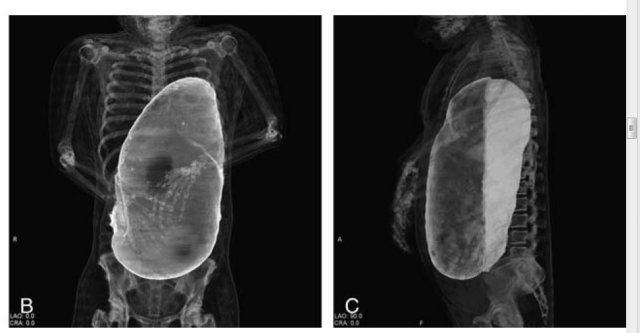

20인분 이상 먹고 사망한 사람의 X레이사진

지난해 미국의 19세 여성은 음식을 많이 먹은 뒤 위가 커진 상태에서 구토를 하다가 위와 식도가 찢어져 숨진 일도 있다. 2016년 일본에선 20인분을 넘게 먹은 한 60대 여성이 평소보다 위가 40~50배 커져 심장으로 들어가는 혈관을 눌러 혈류장애로 사망하기도 했다.